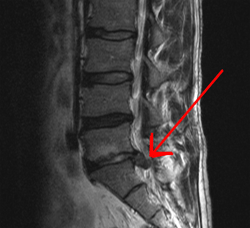

Spinal disc herniation refers to tear in annulus fibrosis and protrusion of nucleus pulposus from within the disc. It is a degenerative disorder of the spine. The patient may present with back pain. The investigative modality of choice for herniated spinal disc is MRI. It has an accuracy of 97%.